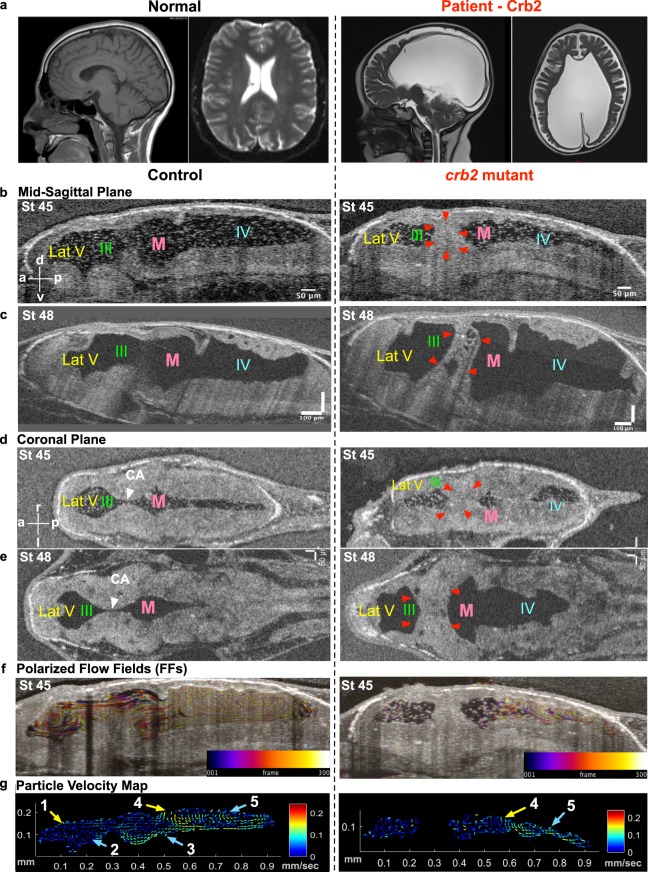

Figure 5. Hydrocephaly phenotype with CRB2 mutations. (a) CT scan of a normal brain and patient brain, with enlargement of the brain ventricles. (b) Mid-sagittal view (d) Coronal view using OCT shows reduction in ventricular size along with CA stenosis in crb2 F0 CRISPR mutant tadpole brain at stage 45 as compared to controls. (c) Mid-sagittal view (e) Coronal view of control and crb2 F0 CRISPR mutant tadpole raised to stage 48 shows enlargement of the ventricles as compared to controls. This result was seen in 3 animals that survived to this later stage. (White arrow head â CA, red arrowheads â stenosis of CA). (f) Stage 45 tadpole particle tracking shows the impairment of the flow fields in the lateral 3rd and midbrain ventricles, but normal flow in the fourth ventricle for the crb2 F0 CRISPR mutant as compared to the control. (g) 2D Particle Velocity Map shows loss of FFs 1-3 and intact FFs 4-5. (Lat-V: lateral ventricle, III: 3rd ventricle, M: Midbrain ventricle, IV: 4th ventricle).